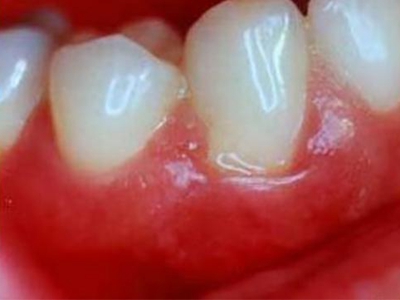

慢性龈炎又称边缘性龈炎或单纯性龈炎,主要表现为游离龈和龈乳头因炎性水肿,而变为鲜红或暗红色,龈缘变厚,龈乳头圆钝肥大。慢性龈炎的患病率高,治愈后仍可复发,部分患者可发展成为牙周炎。

慢性龈炎的病损部位一般局限于游离龈和龈乳头,以前牙区为主,尤其以下前牙区最为显著,患者常因刷牙或咬硬物时牙龈出血而就诊。游离龈和龈乳头颜色变为鲜红或暗红色,病变较重时炎性充血可波及附着龈。龈缘变厚,龈乳头圆钝肥大,可增生呈球状,覆盖牙面。牙龈松软脆弱,缺乏弹性。

当牙龈以增生性反应为主时,龈缘和龈乳头呈坚韧的实质性肥大,质地较硬而有弹性。龈沟液量增多,还可能出现龈沟溢脓现象。